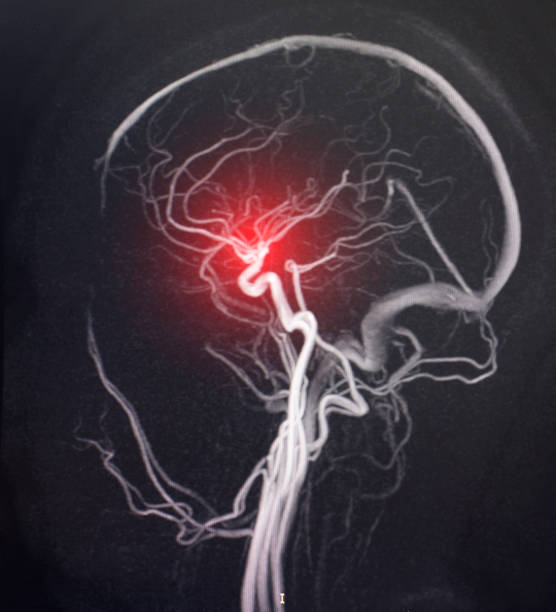

뇌경색은 뇌혈관이 막히면서 해당 부위에 혈액이 공급되지 않아 뇌세포가 손상되는 질환이에요.

**‘허혈성 뇌졸중’**이라고도 하며, 전체 뇌졸중의 약 **70~80%**를 차지할 만큼 흔한 형태입니다.

보통은 고혈압, 당뇨, 고지혈증, 흡연, 심장질환 등이 주요 원인으로 작용하죠.